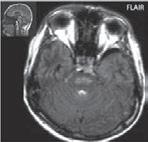

Obr. I.1.8a Dandy-Walkerova malformace, rozšířená IV komora (tvar klíčové dírky)

Obr. I.1.8b Dandy-Walkerova malformace, rozšířená IV komora široce komunikující s cisterna magna, hypotrofie mozečku (snímky zapůjčeny z archivu prim doc MUDr M Mechla, Ph D, MBA)

Obr. I.1.8c Dandy-Walkerova malformace, rozšířená IV komora široce komunikující s cisterna magna, hypotrofie mozečku (snímky zapůjčeny z archivu prim doc MUDr M Mechla, Ph D, MBA); stejný pacient jako na obr I 1 8b

Obr. I.1.8d Dandy-Walkerova malformace, rozšířená IV komora široce komunikující s cisterna magna, hypotrofie mozečku, vysoký úpon tentoria (šipka) (snímky zapůjčeny z archivu prim doc MUDr M Mechla, Ph D, MBA); stejný pacient jako na obr I 1 8b, c